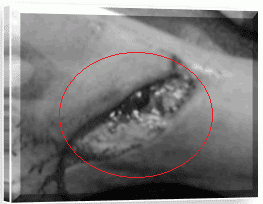

- Vulnus laceratum atau luka robek adalah luka dengan tepi yang tidak beraturan, biasanya oleh karena tarikan atau goresan benda tumpul.

Vulnus laseratum adalah luka robek yang tidak beraturan yang terjadi akibat kekerasan benda tumpul sering diikuti alat dalam seperti patah tulang.